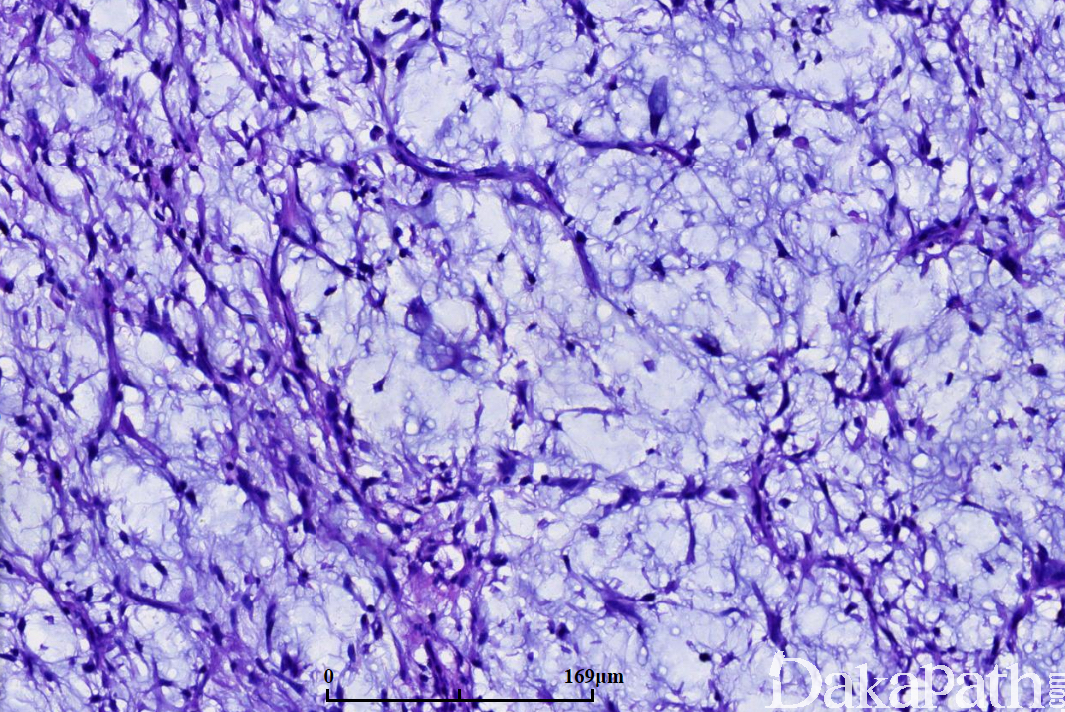

- 低度恶性黏液纤维肉瘤:

- 肿瘤边界不清,细胞密度低;

- 主要由梭形细胞或星状细胞组成,细胞排列紊乱或呈条束状排列,胞质常呈淡嗜伊红色,核深染,有轻度异型,核分裂像不多见;

- 常常可见到多空泡状的假脂肪母细胞;

- 部分病例内可见核深染的多核瘤细胞或畸形瘤细胞;

- 肿瘤内的血管多呈细长的曲线状或弧线状,少数病例中也可呈丛状或分支状,瘤细胞有沿血管排列的倾向。